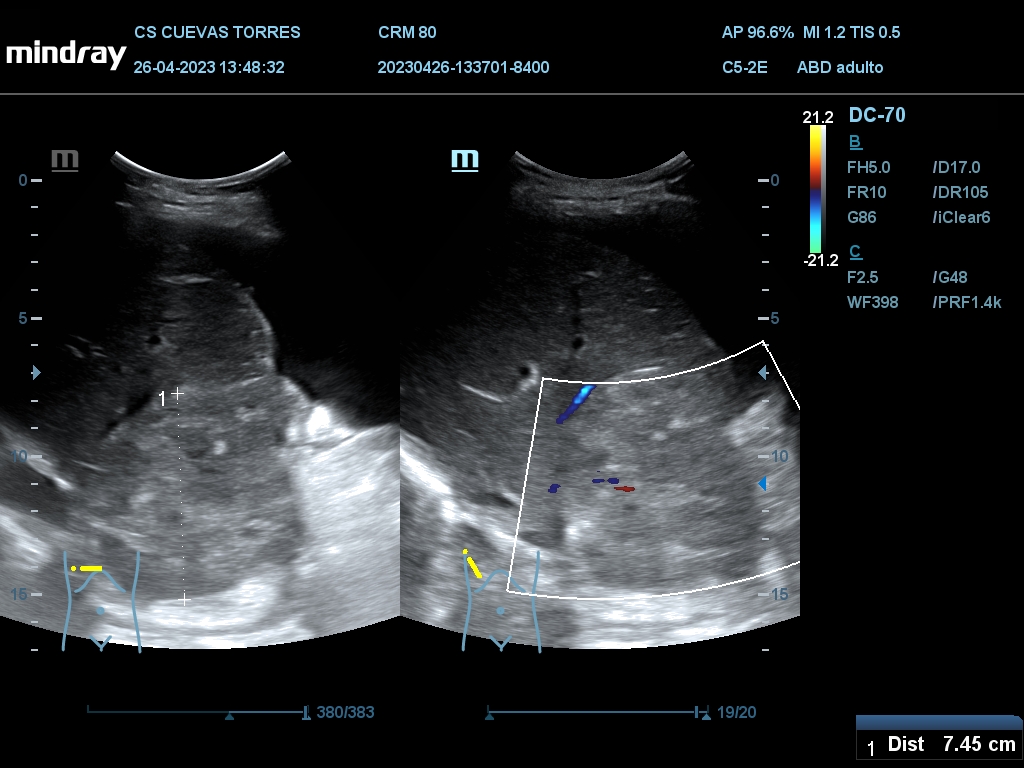

En la ecografía clínica observamos claramente la presencia de líquido libre desde el comienzo de la exploración. Continuando con el estudio Visualizamos circulación portal turbulenta y en el rastreo hepático una lesión ocupante de espacio (LOE) con captación Doppler de 7,45 cm de diámetro máximo.